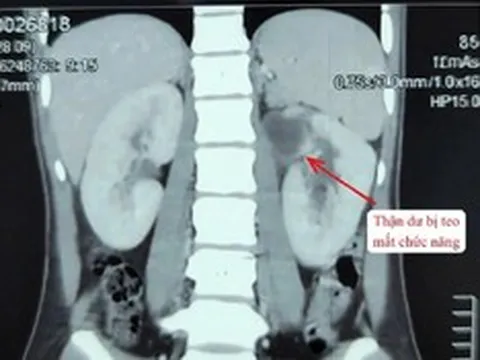

Theo Healthline, lạm dụng thuốc giảm đau gây hậu quả nghiêm trọng: Tổn thương gan, thận, tim mạch (cao huyết áp, đột quỵ), xuất huyết tiêu hóa, loét dạ dày và có thể dẫn đến nghiện thuốc, trầm cảm, hoặc thậm chí tử vong, đặc biệt nguy hiểm khi kết hợp các loại thuốc hoặc dùng sai liều/thời gian.

- Gây hại cho thận: Uống thuốc giảm đâu thường xuyên sẽ gây hại cho thận bởi thận là cơ quan bị tác hại nặng nhất nếu lạm dụng thuốc giảm đau. TS Shah nói, vì thuốc giảm đau ức chế sự tổng hợp prostaglandin, việc sử dụng mạn tính có thể dẫn đến suy thận. Từ đó, khiến lưu lượng máu đến thận kém, dị ứng cấp tính với thuốc giảm đau biểu hiện ở thận, khiến protein tràn ra nước tiểu.